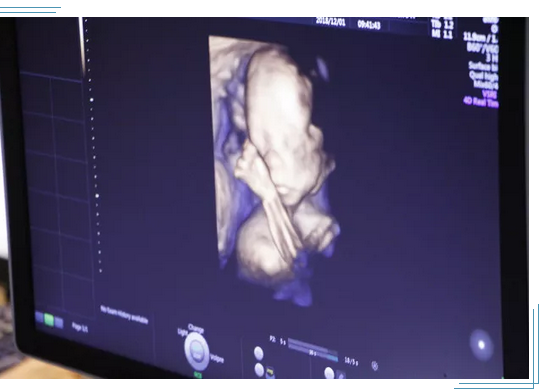

大连做四维彩超多少钱?孕中期(22~28周)做四维彩超检查可以清晰了解胎儿的面部发育状况,筛查无脑儿、严重脑膨出、严重脊柱裂等胎儿发育异常状况。那么,大连做四维彩超多少钱?

四维彩超在当代已经可以实现立体、实时观察胎儿活动图像。在孕期,四维彩超可以帮助孕妇排查胎儿是否有畸形。那么,这样的彩超和传统的B超相比,价格自然也会相对高一些。通常在300—400元之间,但是每个地区和医院的价格都有所差异,具体还要按照当地的医院而定。

2、4D超声可多方位、多角度地观察宫内胎儿的生长发育情况,为早期诊断胎儿先天性体表畸形提供准确的科学依据,可以实时清晰地观察宝宝动态运动。它不存在射线、光波和电磁波等方面的辐射,高分辨率容积成像(HD Live)、容积SRI (V SRI),新一代的4D 渲染模式,图像质量卓越。